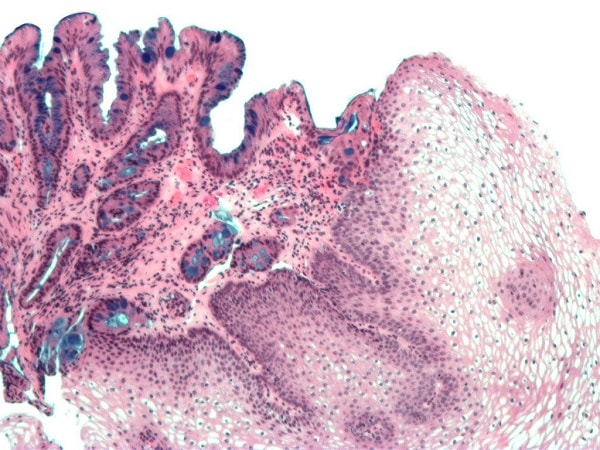

Để hiểu được bệnh thực quản Barrett, trước tiên cần phải hiểu được hình dạng bình thường của thực quản. Ở dạng bình thường, lớp lót mô thực quản có màu hồng nhạt và mịn. Những tế bào lát vuông, gọi là tế bào lát, tạo nên lớp lót bình thường của thực quản.

Ngược lại, thực quản Barrett có lớp tế bào lót có màu cá hồi , được tạo thành từ các tế bào tương tự như các tế bào trong ruột non và được gọi là "chuyển sản bất thường tế bào ruột".

Nội soi là xét nghiệm được lựa chọn để chẩn đoán bệnh thực quản Barrett. Trong quá trình nội soi, một ống mỏng có gắn nguồn sáng và máy ảnh ở đầu ống được đưa qua miệng, xuống cổ họng và vào dạ dày của bạn. Sinh thiết mẫu mô ở thực quản để nhìn dưới kính hiển vi cũng được thực hiện trong quá trình nội soi. Mô thực quản có nhiều loại tế bào bất thường nhất định là tiêu chuẩn cần thiết để chẩn đoán thực quản Barrett và là một trong những chìa khóa để quản lý bệnh Barrett.

Chìa khóa để kiểm soát bệnh thực quản Barrett là mức độ loạn sản mà mẫu sinh thiết cho thấy. “Loạn sản" nghĩa là có bao nhiêu tế bào chuyển thành tế bào tiền ung thư. "Không có loạn sản" nghĩa là tế bào Barrett không chuyển thành tiền ung thư. Loạn sản bậc thấp có nghĩa là các tế bào cho thấy một số đặc điểm ban đầu của bệnh ung thư. Loạn sản bậc cao có nghĩa là các tế bào biểu hiện nhiều thay đổi về ung thư. Loạn sản càng nhiều, nguy cơ mắc bệnh ung thư từ thực quản Barrett càng cao.

Trong sinh thiết không có loạn sản, các nhân tế bào nhỏ, được sắp xếp liên tục và nằm ở đáy của tế bào Barrett. Hầu hết những người có thực quản Barrett và không có tình trạng loạn sản tế bào sẽ phải nội soi nhiều lần trong tương lai để đảm bảo rằng tình trạng này không tiếp tục tiến triển nữa. Theo dõi nội soi ở người mắc bệnh thực quản Barrett không có loạn sản thường được khuyến cáo thực hiện trong 3-5 năm, nhưng bác sĩ sẽ quyết định xem điều gì tốt nhất cho bạn.